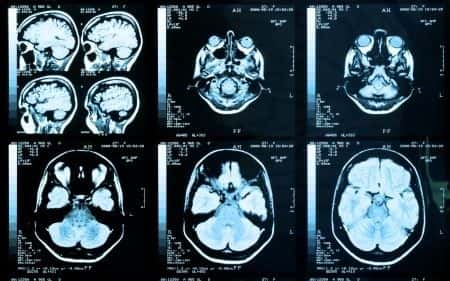

This case involves a female patient who fell and sustained a blow to the head. The patient was on Coumadin therapy for atrial fibrillation. When she arrived at the emergency room, CT head imaging showed an evolving subdural hematoma. The patient needed to be transferred to a tertiary care center for further treatment, but, in transit, the patient was never given vitamin K or fresh frozen plasma to reverse the effects of the anticoagulation. The patient’s bleed progressed rapidly before surgical intervention could be attempted. The patient suffered from brain herniation and death due to a massive hematoma.

For patients receiving warfarin who've suffered a minor head injury, an initial CT scan needs to be performed. That should be followed by twenty-four-hours of observation, and a second CT scan, which will identify most occurrences of delayed bleeding. An initial international normalized ratio greater than three suggests higher risk. In this patient's case, the head CT was indicative for a major bleed, therefore more advanced measures should have been initiated. These could include vitamin K and fresh frozen plasma as reversal agents to attempt to stop the bleed from progressing.